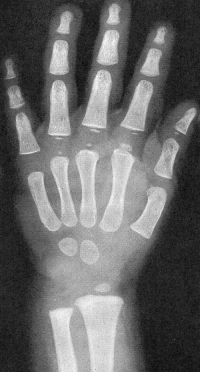

Sexo Feminino

5 anos

Sexo Masculino